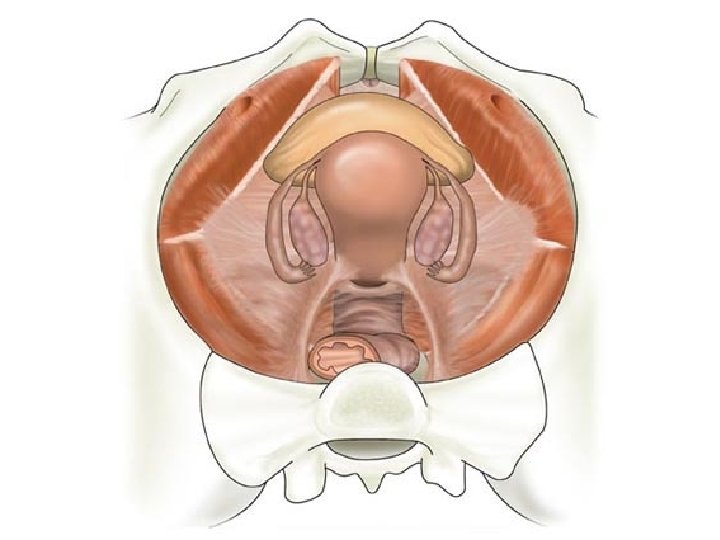

INTERNAL ACCESSORY ORGANS • • Vagina Uterus Uterine tubes Overies

Vagina (Kolpos) • • Fibromuscular tube about 9 cm Fornix vaginae Columna rugarum Tunica mucosa Tunica muscularis Tunica adventisya A. vaginalis V. iliaca interna Vajina

Uterus (Metra - Hystera) • 8 x 6 x 4 cm 40 -50 g. • Corpus, isthmus, collum (cervix) • Portio vaginalis uteri

• • • Serosal layer (perimetrium) Muscular layer (myometrium) Mucosal layer (endometrium) Excavatio vesicouterina Excavatio rectouterina (Douglas )

Tuba Uterina (Fallop Tüpleri-Salpinx) • İnfundibulum (fimbria, fimbriae ovarica) pars ampullaris, isthmica, interstitialis • A. ovarica ve A. uterina

Ovaries Medulla (blood and lenf vessels, nerves) Cortex (germinal epitel, tunica albuginea, hilum ovarii) Lig. Ovarii Proprium (between overies and uterus) Lig. Suspensorium Ovarii (infundibulopelvic) (between overies and pelvic side wall) • A. ovarica, plexus pampiniformis • •